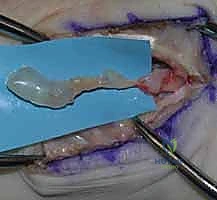

المرحلة الثالثة: الاستئصال الدقيق (Enucleation)

هنا تبرز مهارة الجراح الخبير. يقوم الدكتور هطيف بعمل شق مجهري في الغلاف الخارجي للعصب (Epineurium) في منطقة خالية من الألياف العصبية الحيوية. باستخدام أدوات ميكروسكوبية دقيقة جداً، يتم فصل الورم بلطف عن الألياف العصبية السليمة واستخراجه ككتلة واحدة دون قطع أي حزمة عصبية رئيسية. يتم إرسال الورم مباشرة إلى مختبر الباثولوجي (علم الأمراض) لتأكيد نوعه.